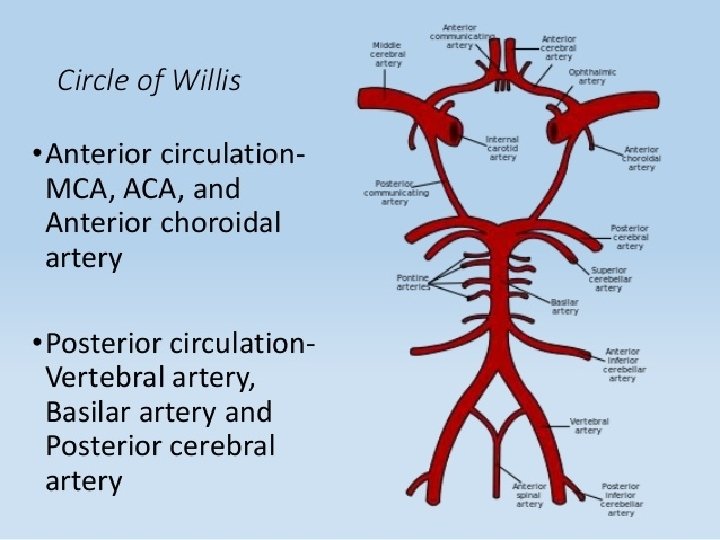

Types of Stroke Depending upon the blood supply of affected area of brain, stroke can be of following types: § ANTERIOR CIRCULATION STROKE: Carotid system § POSTERIOR CIRCULATION STROKE: Vertebrobasilar system

MIDDLE CEREBRAL ARTERY • Supplies lateral surface of frontal, perital and temporal lobes • Most of the motor and sensory cortex Ecxept the part on medial side and control lower limb, internal capsule Total Occlusion: • Uncrossed hemiplegia • Hemianesthesia • Global Dysphasia • Homonymous hemianopia • Apraxia, Agnosia Partial occlusion: • Any of the above features. • Lower limb is either not or minimally involved

ANTERIOR CEREBRAL ARTERY • Supplies MEDIAL surface of hemisphere • Motor and sensory cortex on medial side which control lower limb • Soon its origin it gives a penetrating branch (Heubner’s artery) which supply internal capsule (containing fibers of upper limb and face) Occlusion at the origin: Features are similar to total occlusion of MCB Occlusion of Heubner’s artery : • Weakness of upper limb and face Occlusion after the origin of Heubner’s artery : • Weakness of lower limb • Loss of cortical sensory function in lower limb

POSTERIOR CEREBRAL ARTERY • Branch of Basilar artery • Supplies occipital lobe which include visual cortex Occlusion: • • Visual field loss Homonymous hemianopia Visual agnosia Disorders of reading Disorders of color vision Memory impairment Motor dysfunction